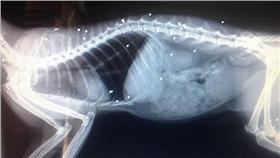

奇蹟!身中41槍 貓咪幸運撿回一命

英國一隻黑貓布思(Puss-Puss)日前走失,沒想...